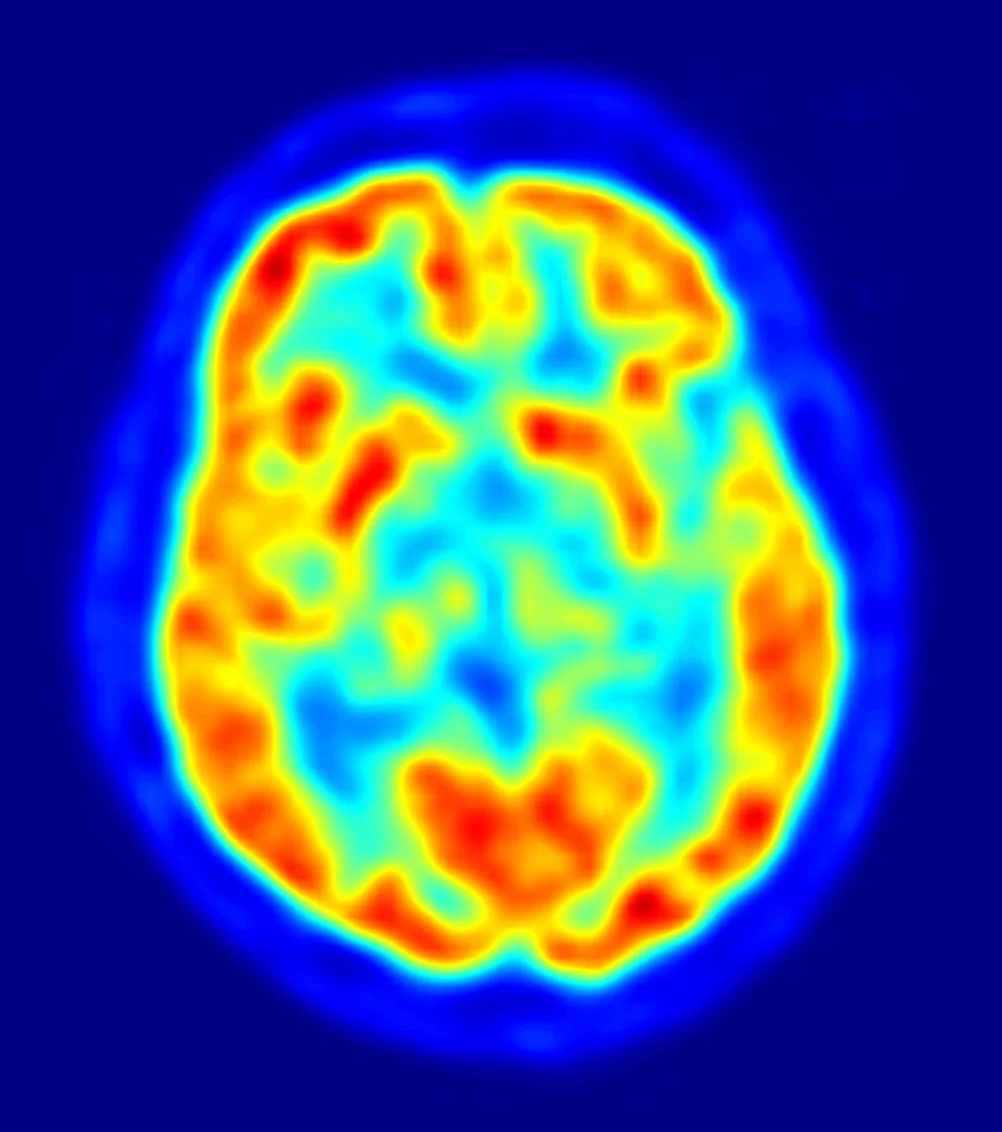

This study was the first research project on CTE ever funded by the National Institutes of Health (NIH), with support from the National Institute of Neurologic Diseases and Stroke (NINDS), the National Institute on Aging (NIA), and the National Institute of Child Health and Human Development (NICHD). The ultimate goal of this study was to develop methods of diagnosing CTE during life through the use of a variety of tests, including MRI scans (such as diffusion tensor imaging), MRS scans (also known as a “virtual biopsy”), blood tests, and measures of proteins in spinal fluid. Participants also underwent neurological, psychiatric, and cognitive assessments, as well as genetic testing.

This longitudinal and cross-sectional study is designed to evaluate the safety and imaging characteristics of 18F-AV-1451 in cognitively healthy volunteers, subjects with Mild Cognitive Impairment (MCI), and subjects with Alzheimer’s Disease (AD). 18F-AV-1451 is a brain imaging agent used in PET (Positron Emission Tomography) Scans. Cognitively healthy participants receive an IV injection of Florbetapir, which is also a PET scanning compound used as a diagnostic tool for Alzheimer’s. Cross-sectional and longitudinal participants will receive a single dose injection of 18F-AV-1451. Only longitudinal participants will receive an IV injection of 18F-AV-1451 at 9 and 18 months. Exploratory MCI Subjects will receive an IV injection of Florbetapir at baseline, followed by an IV injection of 18F-AV-1451 at baseline, 9 months, and 18 months.

This longitudinal and cross-sectional study is designed to evaluate the safety and imaging characteristics of 18F-AV-1451 in cognitively healthy volunteers, subjects with Mild Cognitive Impairment (MCI), and subjects with Alzheimer’s Disease (AD). 18F-AV-1451 is a brain imaging agent used in PET (Positron Emission Tomography) Scans. Cognitively healthy participants receive an IV injection of Florbetapir, which is also a PET scanning compound used as a diagnostic tool for Alzheimer’s. Cross-sectional and longitudinal participants will receive a single dose injection of 18F-AV-1451. Only longitudinal participants will receive an IV injection of 18F-AV-1451 at 9 and 18 months. Exploratory MCI Subjects will receive an IV injection of Florbetapir at baseline, followed by an IV injection of 18F-AV-1451 at baseline, 9 months, and 18 months.